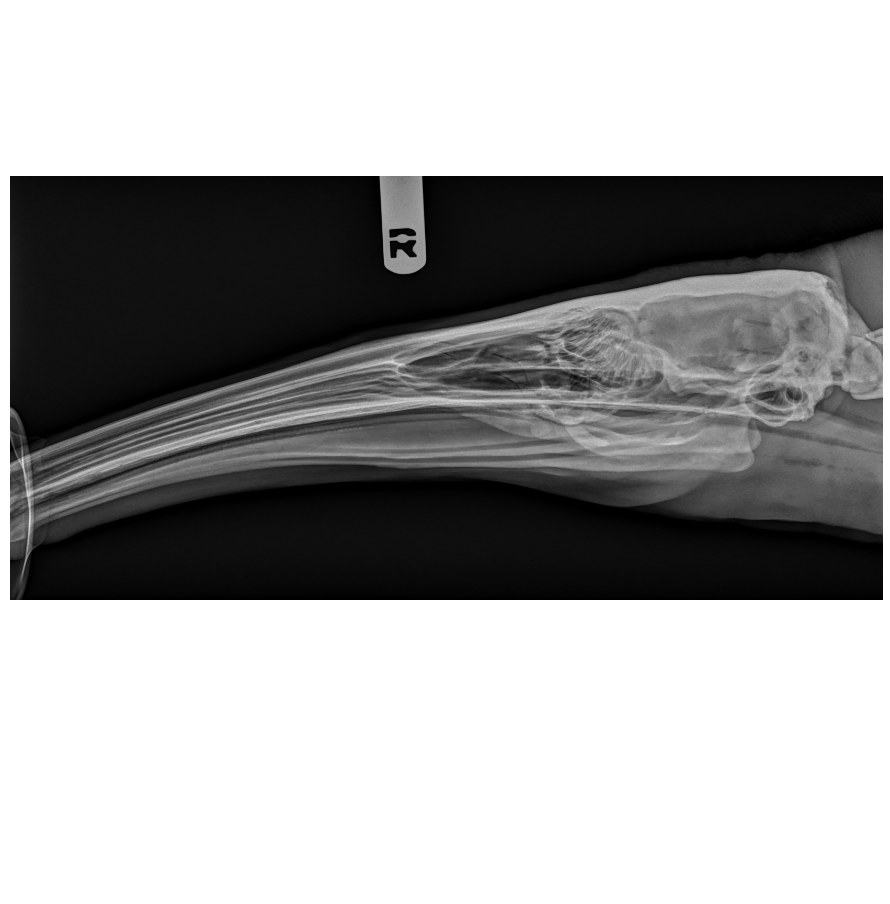

Brookfield Zoo Chicago, San Diego Zoo Wildlife Alliance, Wildlife Conversation Society, Saint Louis Zoo, Disney’s Animals, Science and Environment, Columbus Zoo and Aquarium, and Denver Zoo Conservation Alliance all have joined forces to release the Zoo and Aquarium Radiology Database (ZARD). With support from board-certified radiologists from the Ohio State University College of Veterinary Medicine and the University, the database comprises diagnostic images to help zoological veterinary professionals solve ongoing challenges while advancing the field.

The database will be available to only zoo and wildlife professionals through a web-based user portal and can be searched based on species, age, sex, and body part. There will be over 10,000 diagnostic images featured within ZARD from over 500 different species that are common in zoos, aquariums, or under threat of extinction. There will also be an equal distribution of male and female animals from each species represented at a variety of ages, and each image will be made anonymous to protect the identity of patients. At this point, there are 1,000 images from 50 species in ZARD, but they expect to grow to its targeted goal of 10,000 within the next 2 years.

The ZARD team disclosed that along with the benefits of filling knowledge gaps about the healthy anatomies of these species, the database will also address the fact there is limited availability of radiologists with the skillset needed to read diagnostic images for the species that are in zoological care. According to the release, all the images uploaded to ZARD will be reviewed by radiologists from the Zoo, Exotic, Wildlife Diagnostic Imaging Society of The American College of Veterinary Radiology.1

“Currently there is no textbook to reference to understand the unique anatomies of zoological animals, leaving few radiologists with the experience to confidently assess radiographs," explained Eric Hostnik, DVM, MS, DACVR-DI, DACVR-EDI, the project’s lead radiologist and associate professor of veterinary radiology at the Ohio State University College of Veterinary Medicine.1 “This database will help address the shortage of trained radiologists for these purposes and provide an enormous teaching tool for aspiring veterinarians specializing in zoological medicine and radiology.”